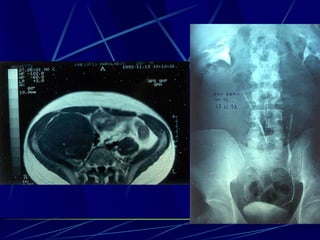

Echinococcus